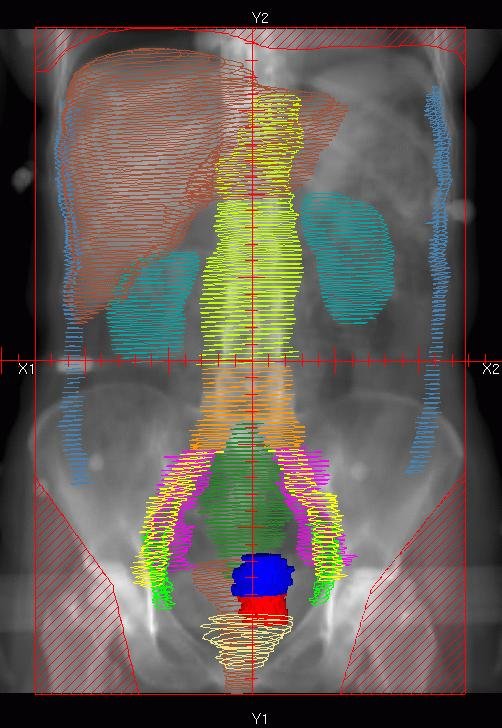

Las distribuciones de dosis en la anatomía real del paciente — obtenidas por cálculo Monte Carlo en imágenes CT — revelan variaciones superiores al 20% en la dosis cutánea, consistentes con medidas in vivo de la literatura. Las líneas de isodosis del 90% (rojo), 75% (blanco) y 50% (azul) revelan blindaje parcial por los brazos elevados, generando discontinuidades en la cobertura entre cabeza y brazo. La distancia entre las isodosis del 90% y 50% es de aproximadamente 5 mm.

Los análisis DVH en tres intervalos de profundidad — 0–5 mm, 5–10 mm y 10–15 mm de la superficie — tanto para el torso como para la piel completa demuestran el impacto del espesor de la placa de dispersión (3 mm versus 9 mm) en la cobertura de dosis. Esta información sobre la distribución volumétrica de dosis es completamente inaccesible por métodos experimentales y representa la contribución singular del Monte Carlo a la planificación de TSET.